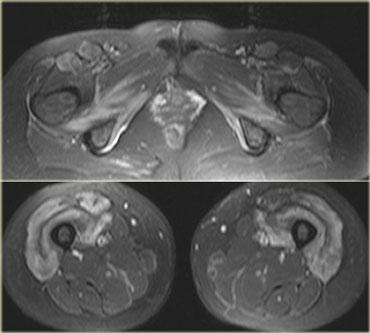

Hình bên trái là một bệnh nhân viêm đa cơ (PM), một trong các thể bệnh cơ viêm.

Các cơ lớn ở gốc chi bị tổn thương, thường theo hình thái đối xứng.

Nhìn chung, không phải tất cả các cơ đều bị tổn thương, do đó MRI có thể giúp xác định vị trí tốt nhất để sinh thiết.

Đôi khi MRI toàn thân được sử dụng để chẩn đoán và theo dõi viêm đa cơ sau khi đã bắt đầu điều trị bằng corticosteroid.

Hình bên trái là một bệnh nhân viêm cơ thể vùi.

Lưu ý tổn thương đối xứng của cơ tứ đầu đùi và sự vắng mặt của phù nề ở các tổ chức xung quanh.